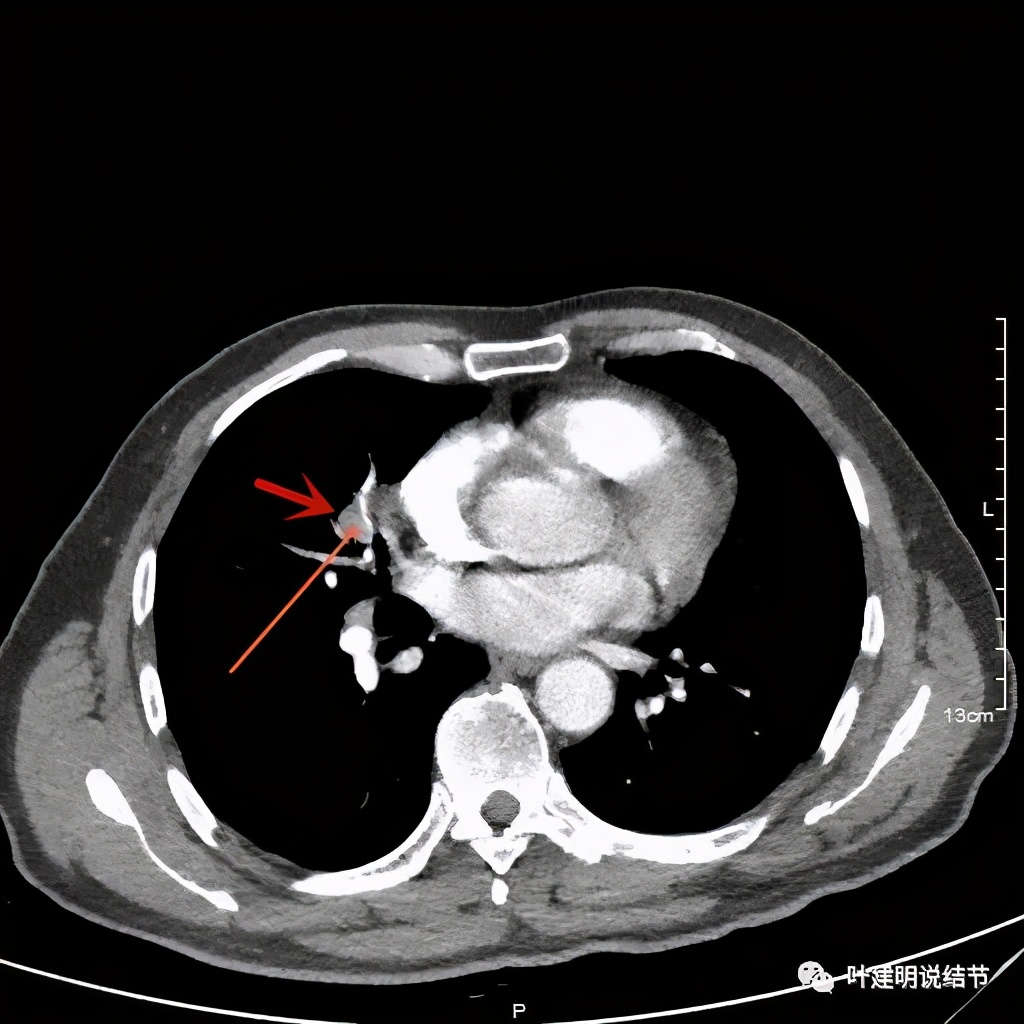

上图示支气管壁欠光整

其实当时也是挺明显的恶性征象的。因考虑肺癌,某A及家属出院后到了上海市肺科医院就诊,打算去手术。结果肺科医院医生一看,除了肺癌还有胰腺肿瘤呀,告诉他要先处理胰腺肿瘤,所以某A又到了上海长征医院住院。医生告诉他如果肺癌与胰腺是两处不相干的肿瘤,那么可以分别处理,若是转移性的,那么要选择化疗,所以建议先做穿刺活检。结果肺与胰腺均穿刺了,病理结果出来两处均是“轻度异型增生”。那怎么办呢?其实也就没有取得足够的组织,不足以判定为肿瘤,但有异常的细胞形态。医生告诉他,接下来两个选择:一是再次穿刺活检;二是观察一个月后再复查。家属一想,这不妥呀,如果再次穿刺仍阴性,不是又回到原点吗?已经2个月了,再观察1个月病灶还能吸收好转?实际上家属也基本认可是恶性的疾病了。另外长征医院的医生也认为肺癌更加要紧点,胰腺占位因为SUV摄取轻度升高,可能是低度恶性肿瘤。应该处理肺癌,它更等不起。当听说他们在金华永康工作时,上海有医生建议他们到金华市人民医院来找我,先解决肺的问题。术前查了肿瘤筛查也有异常: